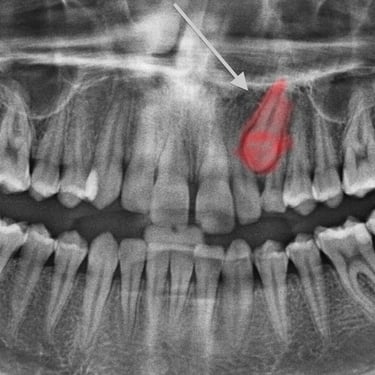

Dientes impactados

Los dientes impactados son dientes que no pueden erupcionar correctamente debido a la falta de espacio o a una obstrucción.

Los pacientes pueden notar que un diente no ha salido, aunque debería haberlo hecho. Esta condición es común con las muelas del juicio y los caninos superiores.

El tratamiento puede incluir la extracción del diente impactado o la creación de espacio para permitir su erupción.